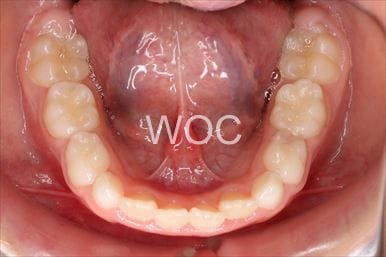

治療前4

治療後4